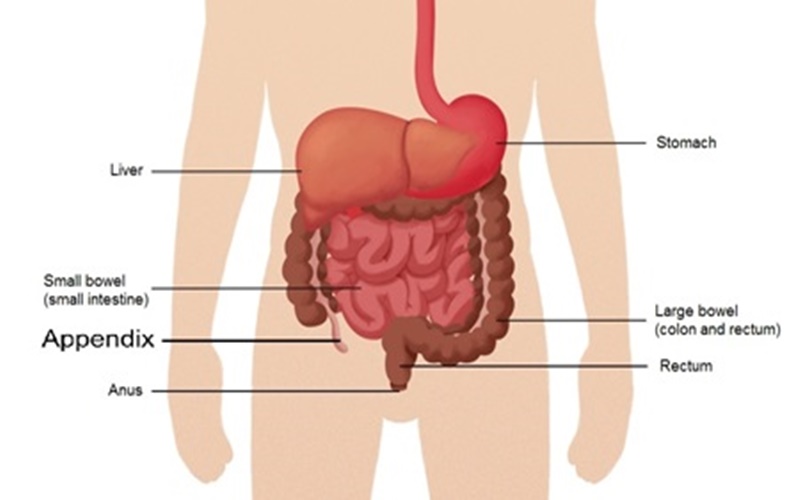

Mengutip Tempo yang melansir dari my.clevelandclinic.org organ yang tidak diketahui fungsinya tersebut merupakan tabung yang ukurannya sebesar jari. Usus buntu terletak pada posisi di mana usus besar dan usus kecil yang saling terhubung. Ketika penyakit usus buntu meradang, rasa sakitnya akan datang terus menerus, kemungkinan bisa sampai pecah dan menyebabkan rasa sakit yang tiba-tiba parah.

Namun makan makanan berserat tinggi dengan banyak biji-bijian dan buah-buahan serta sayuran segar bisa membantu. Sementara itu, yang menjadi tanda utama terjadinya radang usus buntu ialah sakit perut yang parah terjadi di bagian perut kanan bawah yang merupakan tempat usus buntu berada.